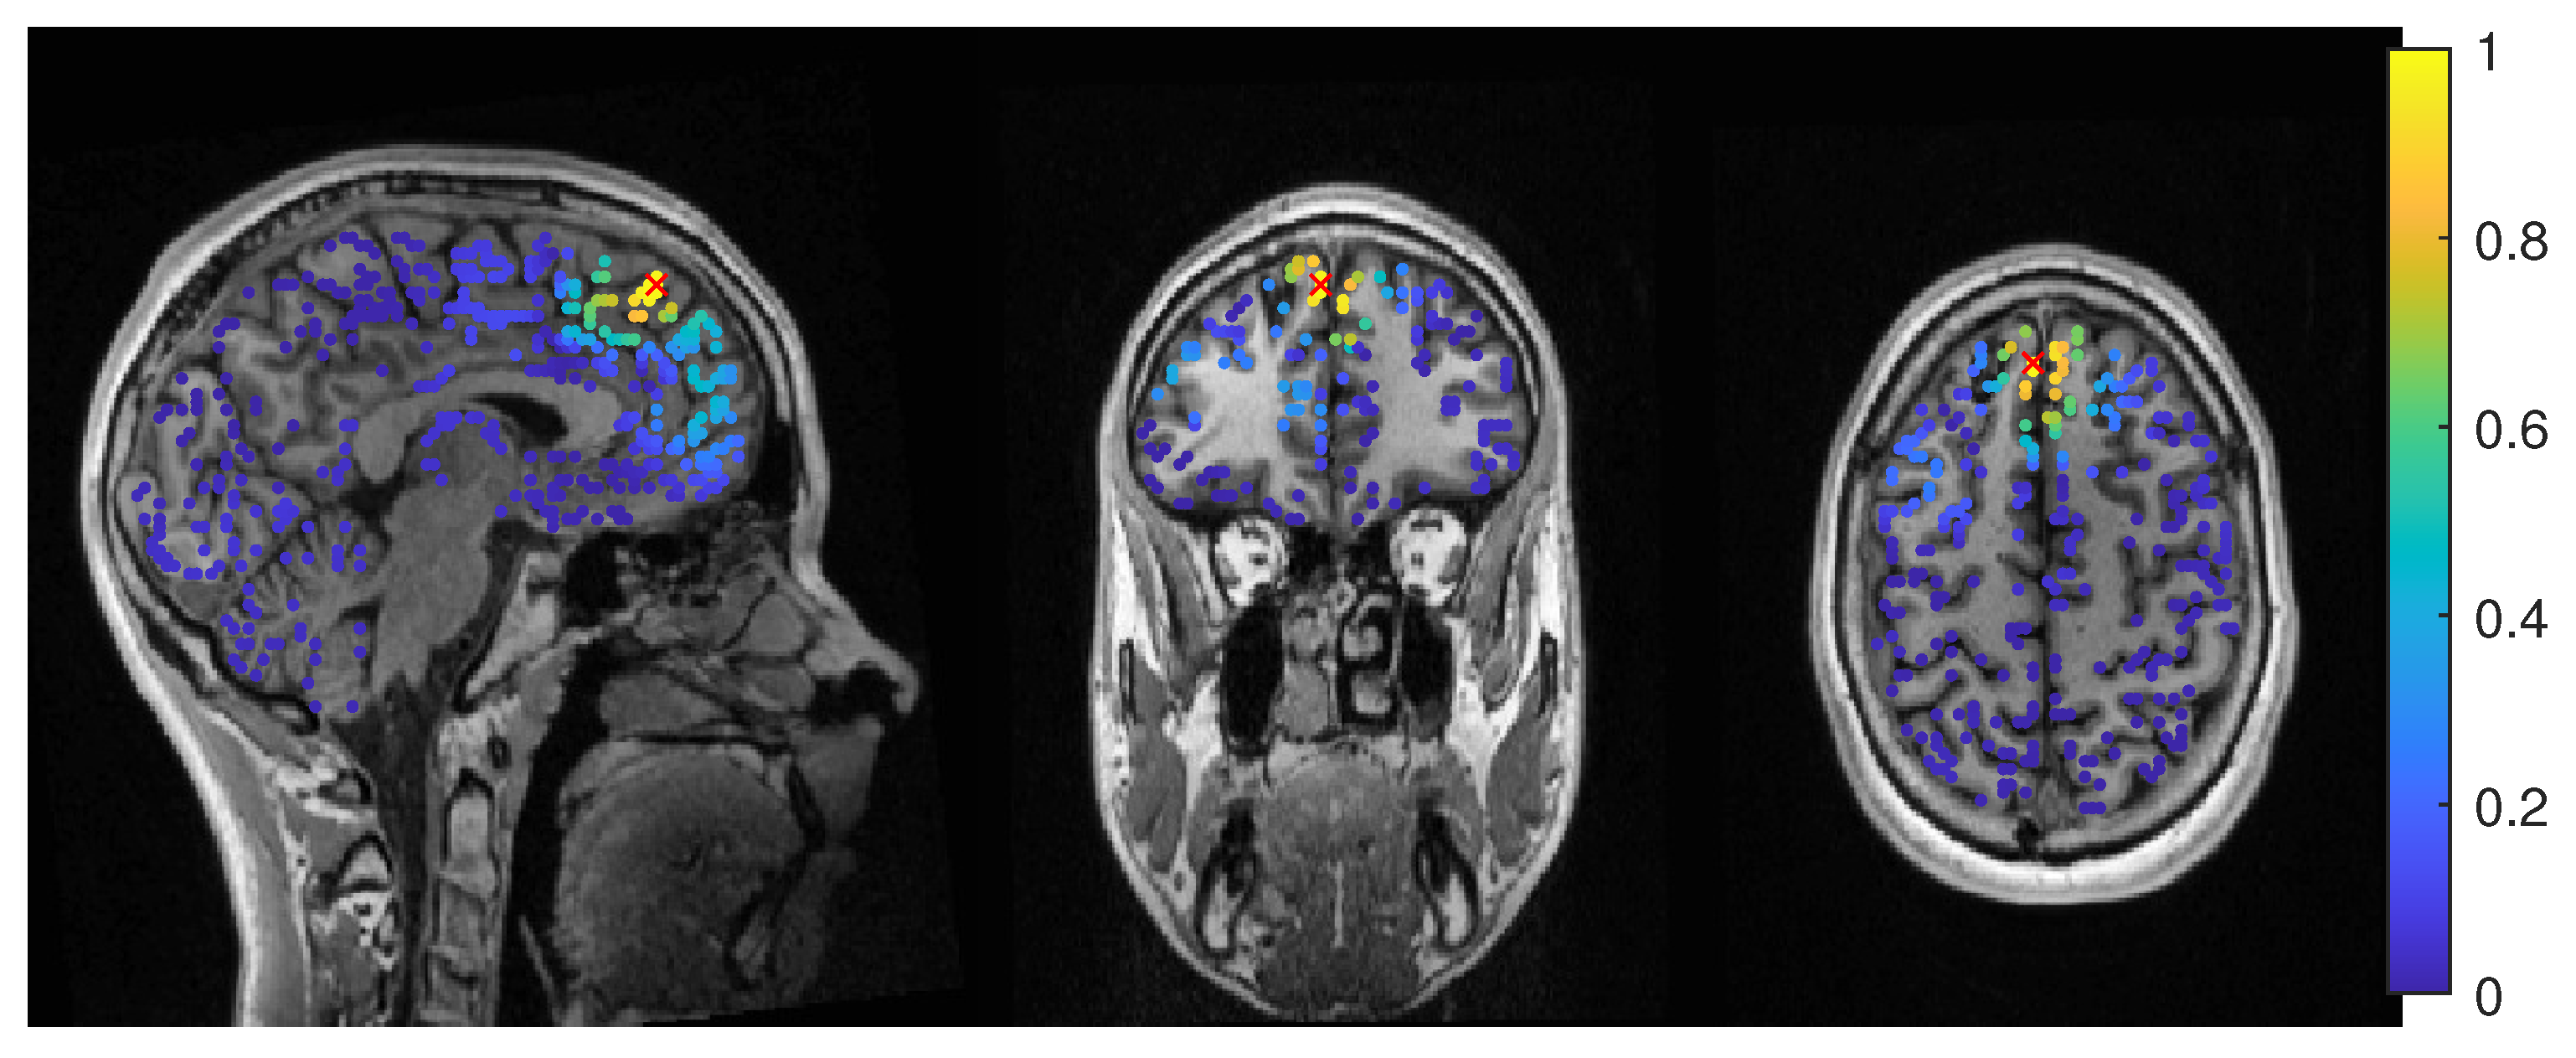

3.1.1. EEG

3.1.2. MEG

3.1.3. MEEG

3.2. Patient 2

3.2.1. EEG

3.2.2. MEG

3.2.3. MEEG